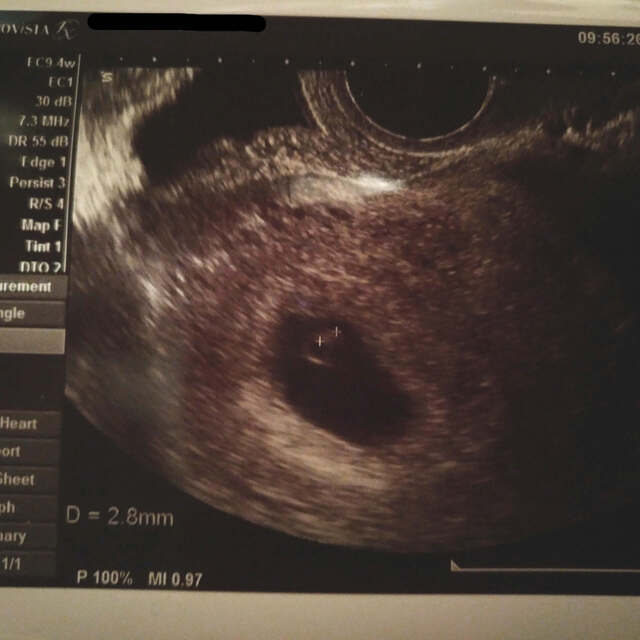

6週0日(6w0d・性別不明)|ぐでみかん さん(28歳)

エコー写真撮影時のエピソード:

初めてのエコー写真!なんだか、まだよくわからない写真だけど感動しました。

卵巣が腫れていると言われて安静を命じられました。

ひどいつわりはなかったけどご飯を炊くにおいと鶏肉を焼くにおいが気になりました。

梅干しを食べると気分が良くなりました。